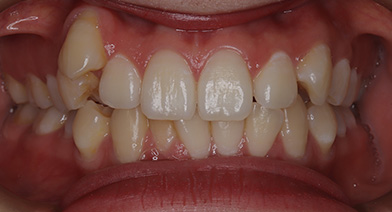

上下顎前歯部叢生症例

- 主訴

- 八重歯、前歯の凸凹、上顎右側犬歯低位

- 診療名

- 13の低位、上下顎前歯部叢生、下顎正中右側偏位

- 年齢・性別

- 20代女性

- 治療期間

- 1年8ヵ月

- 治療説明

- 上下顎大臼歯のアップライト、IPRによるスペースメイキング、17抜歯し、18を咬合させる

抜歯:17番(計1本)

治療装置:インビザライン

固定装置:なし

リテーナー:fixリテーナー+クリアリテーナー

- リスク・副作用

- 痛み・治療後の後戻り・歯根吸収・歯髄壊死・歯肉退縮